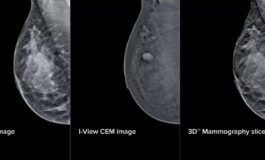

• Mammografia intelligente al San Camillo di Roma aiutera gli specialisti nelle diagnosi 265x160

in Salute & Benessere

Mammografia 'intelligente' al San Camillo di Roma, aiuterà gli specialisti nelle diagnosi

(Adnkronos) - All'azienda ospedaliera San Camillo-Forlanini di Roma la mammografia diventa 'intelligente'. Grazie all'integrazione di intelligenza artificiale e mammografi di ultima generazione, la Uosd Diagnostica per immagini in senologia ha messo a punto "un intervento tecnologico profondo che c...

di Foto profilo di Adnkronos Adnkronos 22 Aprile 2026